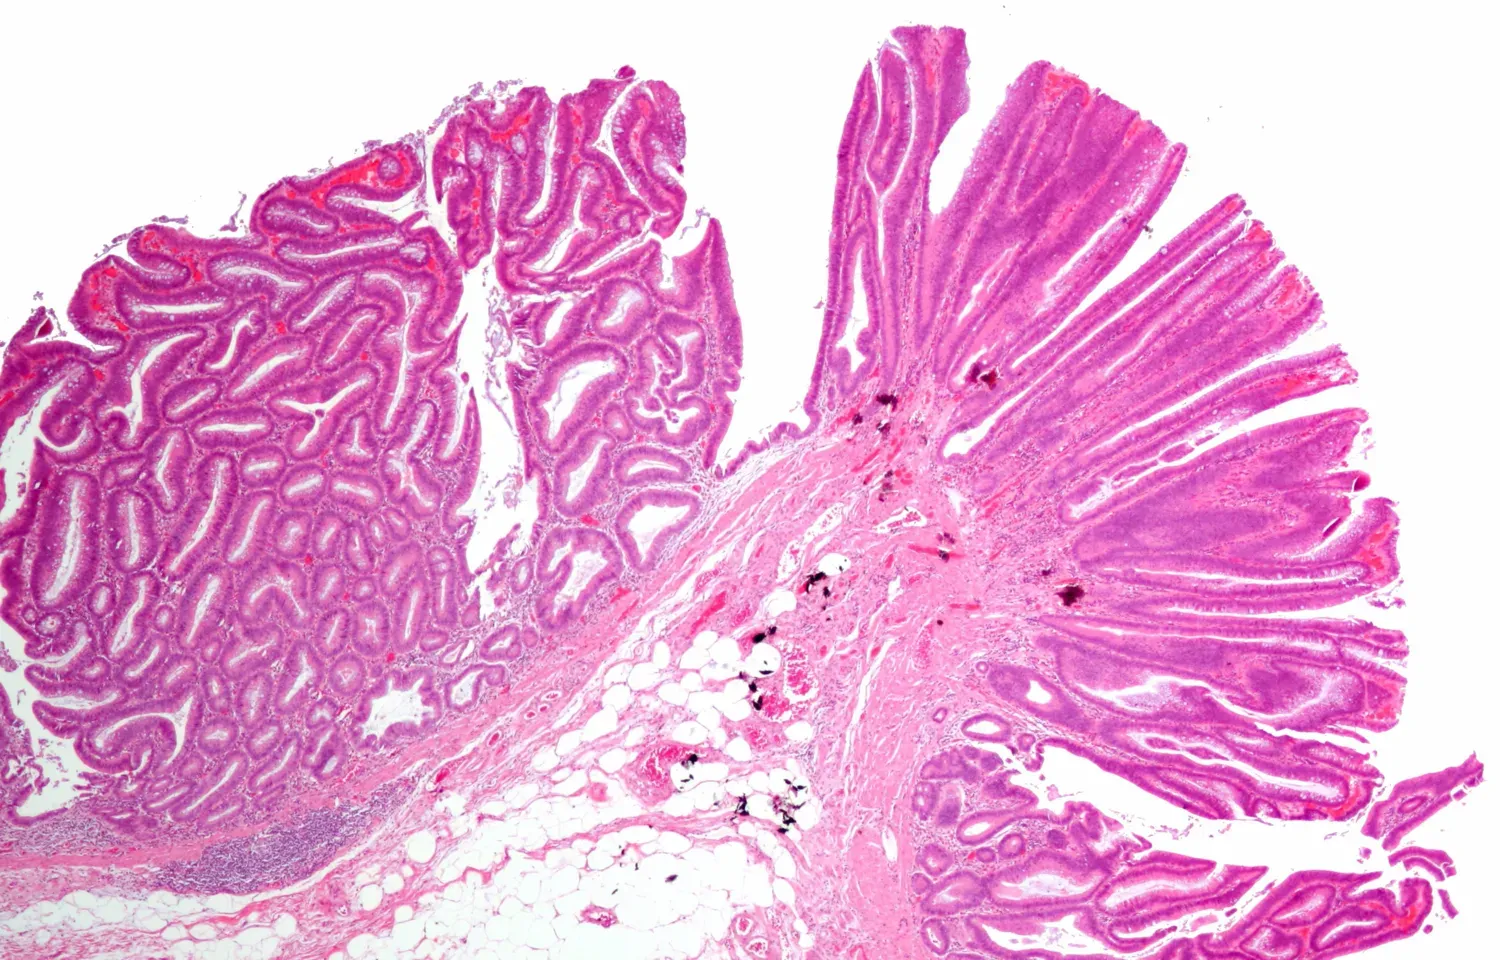

Personer som har inflammatorisk tarmsjukdom (IBD), till exempel Crohns sjukdom eller ulcerös kolit, kan få cellförändringar i tarmen som kallas dysplasi. Dysplasi är ett förstadium till cancer, och ju allvarligare dysplasin är, desto större är risken att utveckla tjocktarmscancer. Det visar en studie av forskare vid Karolinska Institutet, och NYU Grossman School of Medicine, New York, som publiceras i Clinical Gastroenterology and Hepatology.

Forskarna analyserade över 54 000 patienter med inflammatorisk tarmsjukdom (IBD) och redovisar nu de mest omfattande resultaten hittills som rör dysplasi-utveckling och tjocktarmscancer (kolorektal cancer) inom ramen för den nationella ESPRESSO-studien.

Studien visar att bland patienter med IBD utan dysplasi vid studiens start, utvecklade enbart 2,3 procent avancerad neoplasi i tjocktarmen (motsvarar höggradig dysplasi eller tjocktarmscancer) under studiens uppföljning. Avancerad neoplasi i tjocktarmen sågs istället hos en högre andel av IBD-patienter med högre grad av dysplasi (hos 5,3 procent av de med ”indefinite dysplasi” och 8,3 procent av de med låggradig dysplasi).

Hela 40 procent av IBD-patienter med höggradig dysplasi utvecklade tjocktarmscancer, ofta redan inom ett år. Studien fokuserar på ett forskningsområde där det rått stor osäkerhet; långtidsprognosen vid IBD-associerad dysplasi. Forskarna redovisar här nu populationsbaserade risker, något som kan hjälpa läkare att ta hand om patienter med IBD på ett bättre sätt.